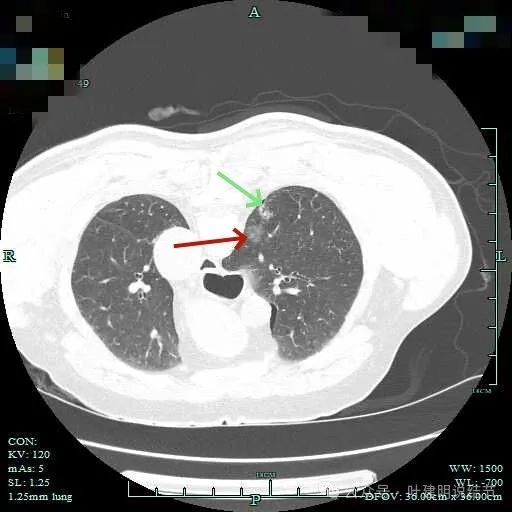

图片

主病灶术前定位,医用胶就在病灶边上(上图绿色的是定位医用胶,红色箭头指的是病灶6)。